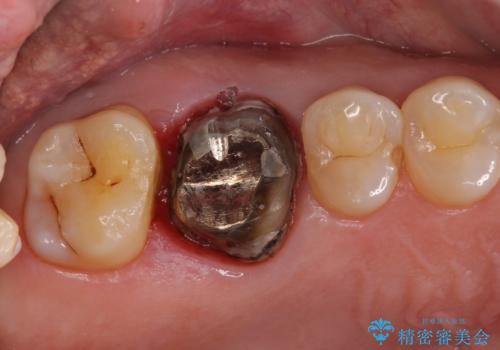

- クラウンが装着された奥歯から、歯磨きの度に出血するとのことで来院された患者様です。

虫歯が歯肉の奥深くにまで及んでおり、歯肉が腫れやすい状態となっていたため、歯肉の切除並びに歯槽骨の形態修正を行い、虫歯が歯肉の外に出てくるようにした上で、オールセラミックにて補綴することとしました。